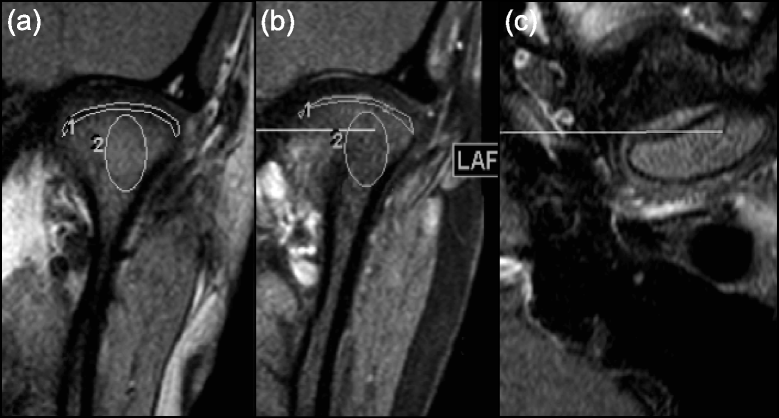

Background: Currently there is no consensus agreement on the degree of enhancement in normal temporomandibular joints (TMJ) in children, which makes it difficult for clinicians to distinguish between the presence/absence of mild synovitis. Quantitative measurements of synovial and condylar enhancement may be useful additions to current qualitative methods on early MRI diagnosis and follow up of TMJ involvement in JIA. The purpose of the study is to establish thresholds/tendencies for quantitative measures that enable distinction between mild TMJ involvement and normal TMJ appearance based on the degree of synovial and bone marrow enhancement in JIA patients.

Methods: TMJ MRI examinations in 67 children with JIA and in 24 non-rheumatologic children who underwent MRI for neurologic/orbit indications were retrospectively assessed. As a priori determined TMJs of JIA patients were categorized into three groups by experienced staff radiologists based on the degree of synovial and condylar enhancement: no active disease (rheumatologic control), mild and moderate/severe findings. The signal intensity (SI) of the synovial tissue around each condyle and of the bone marrow was measured to calculate the enhancement ratio (ER) and relative SI change. The ER was calculated using signal to noise ratios, while relative SI change was calculated using signal intensities alone. Quantitative measurements of synovial and condylar enhancement of TMJs with mild or moderate/severe findings were compared with the rheumatologic and non-rheumatologic controls.